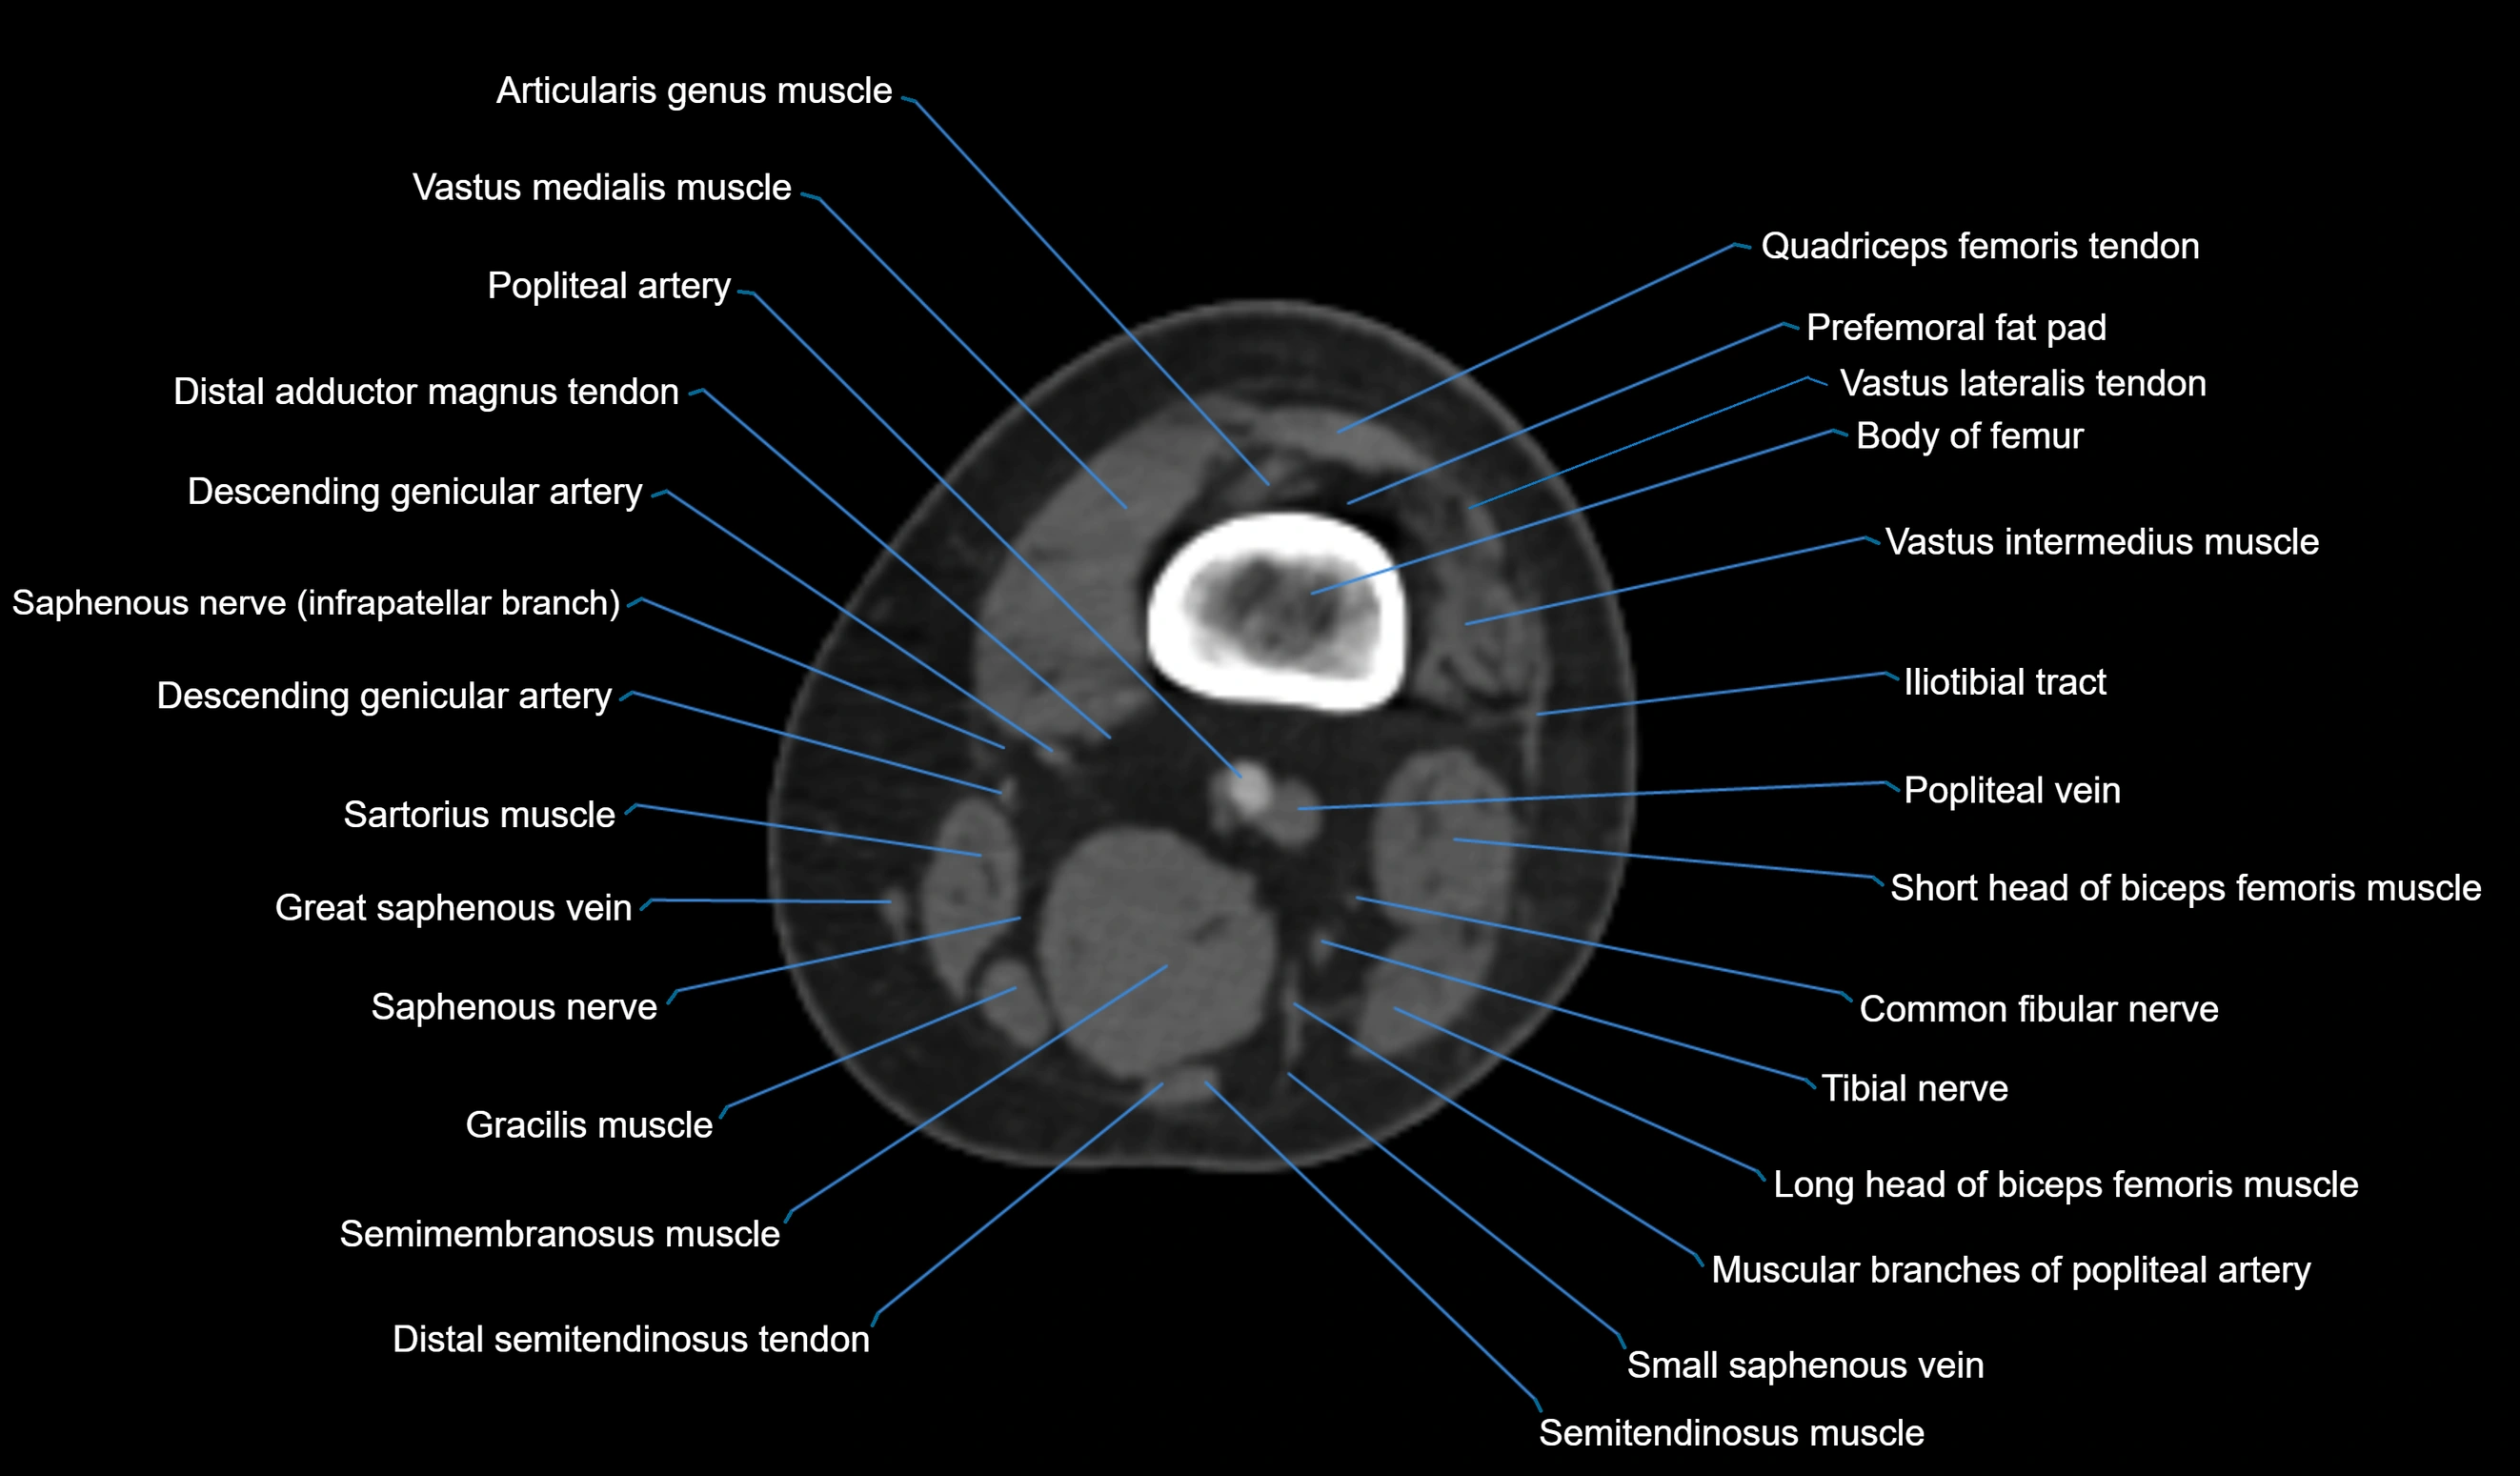

- Biceps femoris muscle (Long head)

- Biceps femoris muscle (Short head)

- Body of femur

- Common fibular nerve

- Descending genicular artery (Articular branches)

- Descending genicular artery (Saphenous branch)

- Distal adductor magnus tendon

- Distal semitendinosus tendon

- Distal vastus intermedius tendon

- Distal vastus lateralis tendon

- Popliteal artery

- Popliteal vein

- Prefemoral fat pad

- Saphenous nerve

- Sartorius muscle

- Semimembranosus muscle

- Semitendinosus muscle

- Small saphenous vein

- Tibial nerve

- Vastus lateralis muscle

- Vastus medialis muscle